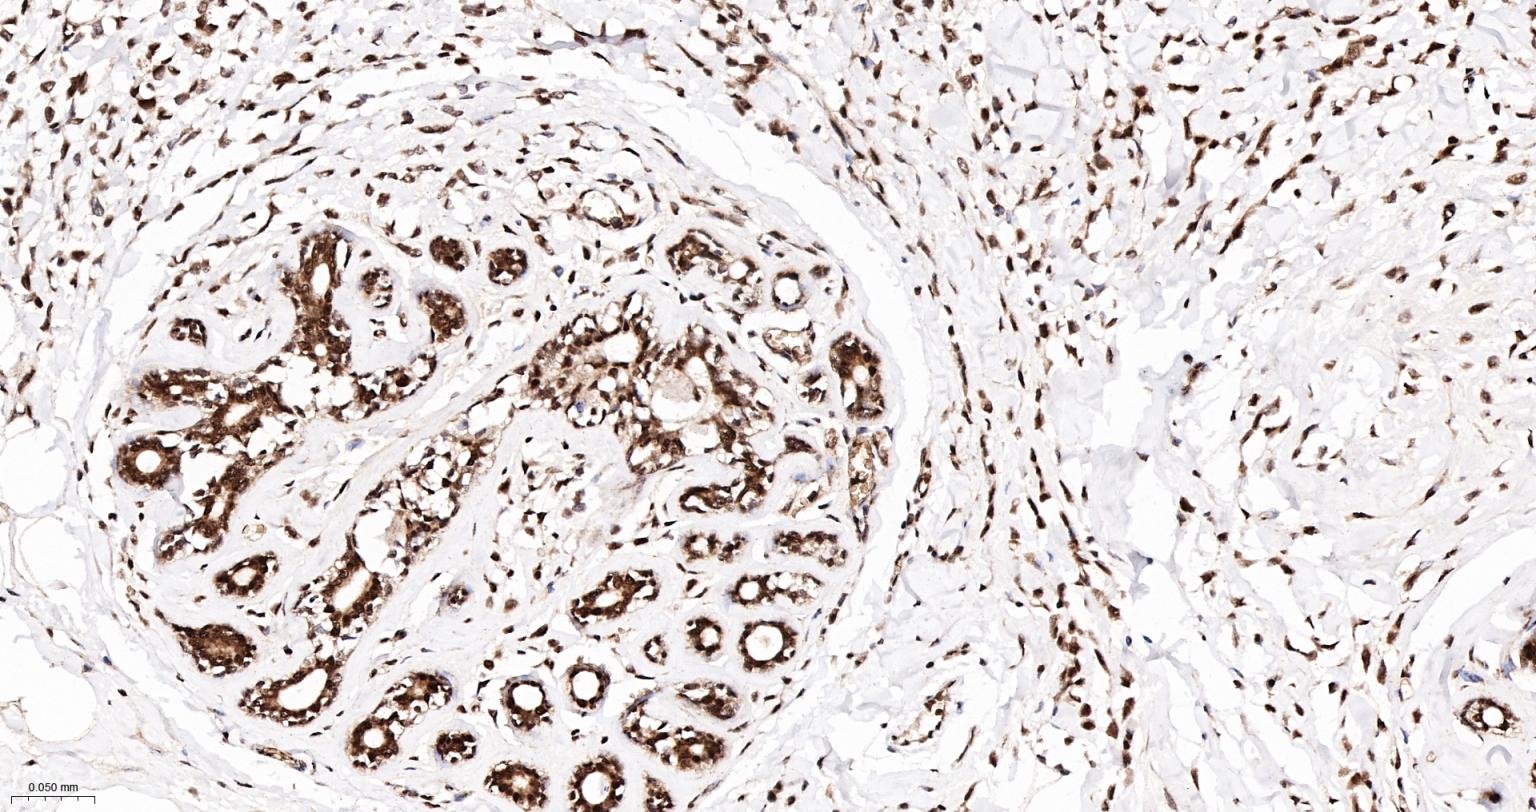

Paraformaldehyde-fixed, paraffin embedded Human Prostate; Antigen retrieval by boiling in sodium citrate buffer (pH6.0) for 15 min; The section was incubated with APEX1 Monoclonal Antibody, Unconjugated (bsm-60707R) at 1:200 overnight at 4°C, followed by conjugation to the bs-0295G-HRP and DAB (C-0010) staining.